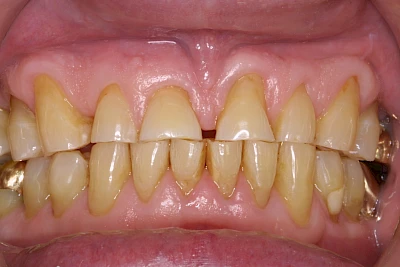

Über die Zeit können verschiedene Prozesse die Zahnhartsubstanzen aufzehren:

- Abnutzung durch Kauen (Abrasion) oder duch durch übermäßiges Knirschen bzw. Pressen (Attrition)

- Säurebedingte Auswaschung (Erosion)

- Knirschen bzw. Pressen und ungünstige Putztechnik (Druck): keilförmige Defekte

Die Zähne können dabei auf Reize (warm, kalt, süß, sauer) oder auch beim Zähneputzen empfindlich oder schmerzhaft sein. In allen diesen Fällen ist es sinnvoll, den Zahnarzt zu kontaktieren und das weitere Vorgehen abzustimmen.